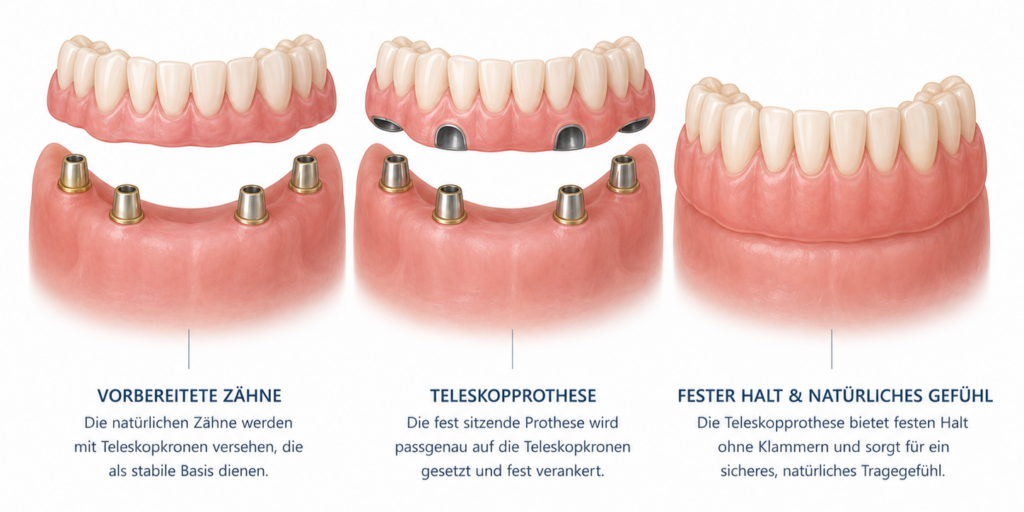

Herausnehmbarer Zahnersatz kommt zum Einsatz, wenn mehrere oder alle Zähne ersetzt werden müssen. Dazu zählen Teilprothesen, Teleskopprothesen und Vollprothesen. Sie lassen sich zur Reinigung herausnehmen und werden individuell an den Kiefer angepasst.

Wenn nur ein einzelner Zahn ersetzt werden muss, kann eine Krone oder eine Brücke infrage kommen. Fehlen mehrere Zähne, sind oft umfangreichere Lösungen notwendig – zum Beispiel herausnehmbarer Zahnersatz oder Zahnersatz auf Implantaten. Auch ästhetische Aspekte und der gewünschte Tragekomfort spielen eine wichtige Rolle.

Im nächsten Schritt werden die Zähne vorbereitet und – je nach Versorgung – Abdrücke genommen oder ein digitaler Scan durchgeführt. Anhand dieser Daten wird der Zahnersatz in einem zahntechnischen Labor passgenau angefertigt.

Festsitzender Zahnersatz wie Kronen oder Brücken kann bei guter Pflege oft viele Jahre, teilweise sogar Jahrzehnte halten. Herausnehmbarer Zahnersatz hat in der Regel eine etwas kürzere Lebensdauer, da er stärker beansprucht wird und sich der Kiefer im Laufe der Zeit verändern kann.